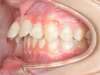

Cas 5 : Description

Absence congénitale des incisives latérales supérieures. Appareils fixes pour créer l’espace nécessaire à la mise en place de facettes en remplacement des latérales.

Après